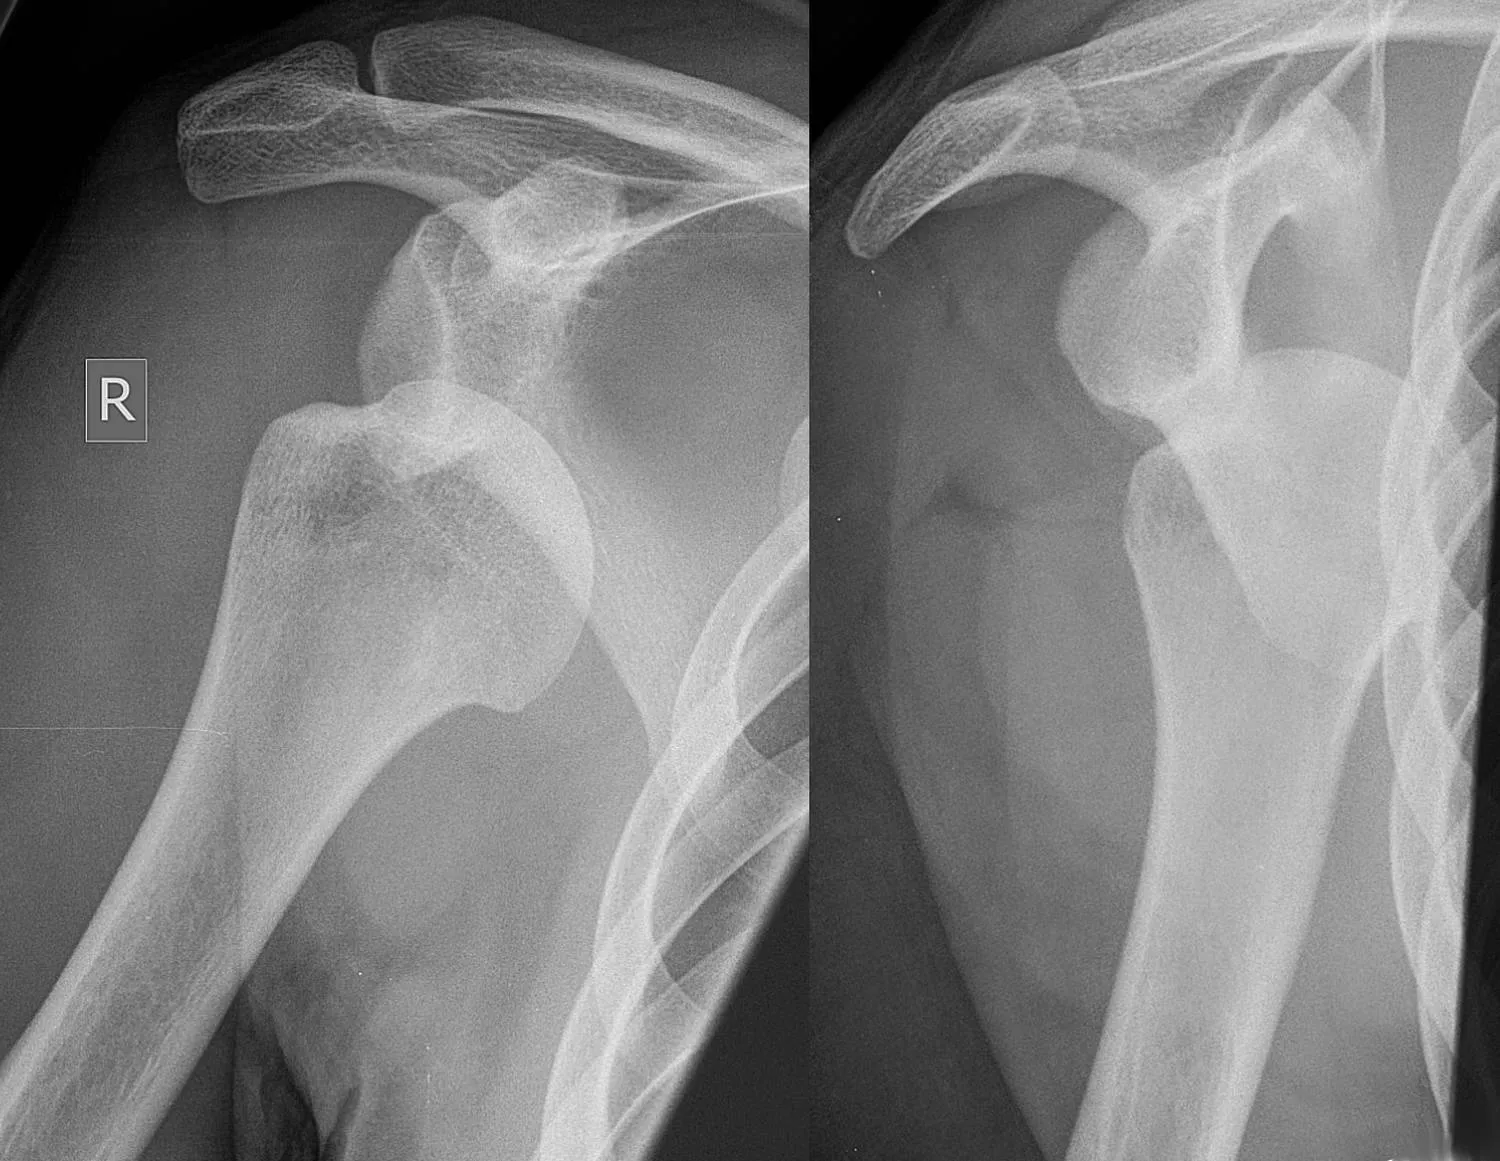

Bárkinél könnyen kialakulhat a leggyakoribb ficam, az emberi szervezet legszabadabban mozgatható ízületét érintő vállficam. Buszon, villamoson, fej felett kapaszkodva, hirtelen fékezéskor, illetve nyújtott karra eséskor a felkarcsont nagy ízületi fejecse kiugrik a lapocka sekély ízületi vápájából.

A sérüléses eredetű ficamoktól el kell különíteni az úgynevezett szokványos ficamot, amely leggyakrabban szintén a vállízületnél fordul elő. Szinte mindennapos sportolóknál, elsősorban tornászoknál, úszóknál. Erőteljes karmozdulatra vagy viszonylag kis erőbehatásra a felkar kiugrik a helyéről. Akinél gyakran előfordul, olykor képes saját magának is helyretenni a kificamodott felkart. Véglegesen csak műtéttel kezelhető.